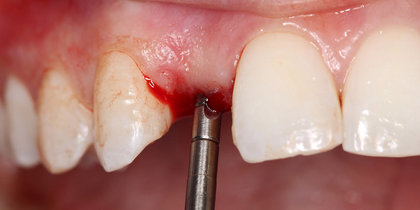

• After extracting tooth #5, a Glidewell HT Implant is immediately placed and a provisional crown delivered, leading to an esthetic, predictable final restoration. thumbnail image

Immediate Provisionalization

After extracting tooth #5, a Glidewell HT Implant is immediately placed and a provisional crown delivered, leading to an esthetic, predictable final restoration.